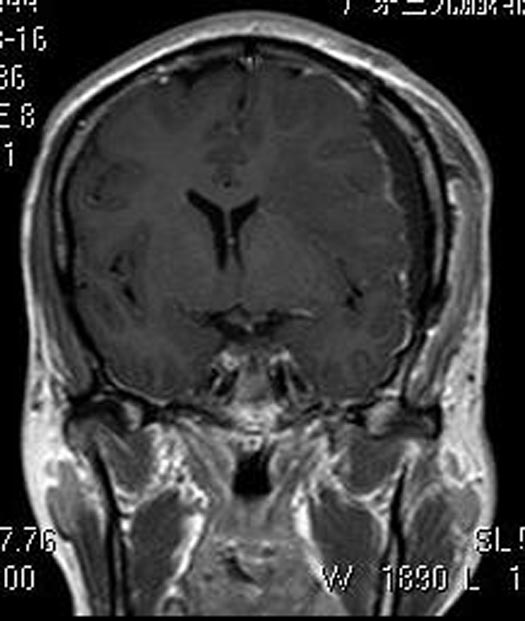

综合神经外科鲁明主任主刀,在全麻下行左侧额颞部脑膜瘤切除术,显微镜下见肿瘤呈灰白色,鱼肉状,质中,边界较清,血供丰富,镜下将肿瘤顺利全切。术后病理结果提示:过渡型脑膜瘤,WHO I级。

▲术后MR